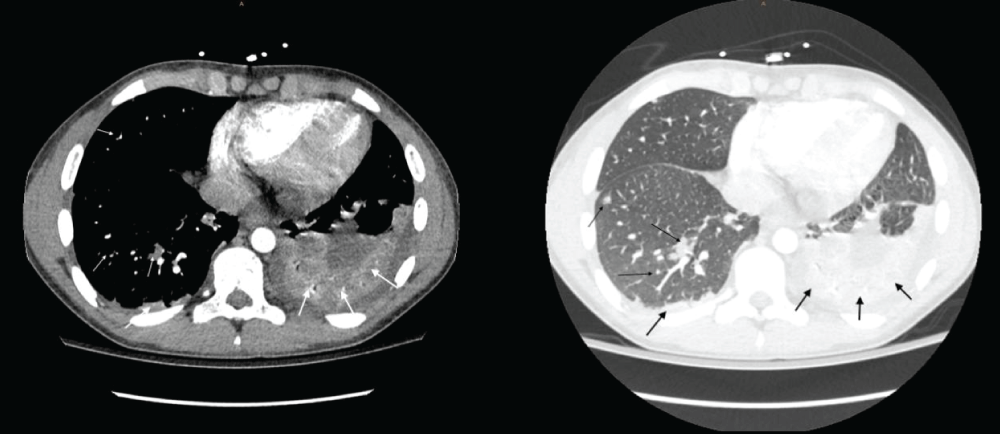

Figure 3:

CT scan showing a small bilateral pleural effusion slightly larger on the left side with passive atelectasis of both pulmonary bases (thick arrows). Multiple bilateral nodular lesions, some of them cavitated, in relation to septic embolisms with an associated pulmonary infarction (thin arrows).